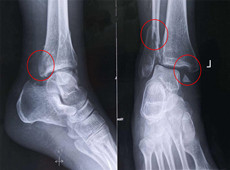

【醫療科普】三維C形臂在足踝手術中的應用優勢

大家好,我是南京醫科大學第二附屬醫院骨科副主任醫師王伯堯,今天我給大家講一講三維C形臂在足踝外科的應用優勢。接下來跟普愛醫療科普小編一起來了解下吧!...

【醫療科普】三維影像:看透關節內骨折的“眼睛”

大家好,我是南京醫科大學第二附屬醫院骨科副主任醫師王伯堯,今天為大家介紹什么是看透關節內骨折的“眼睛”。接下來跟普愛醫療科普小編一起來了解下吧!...